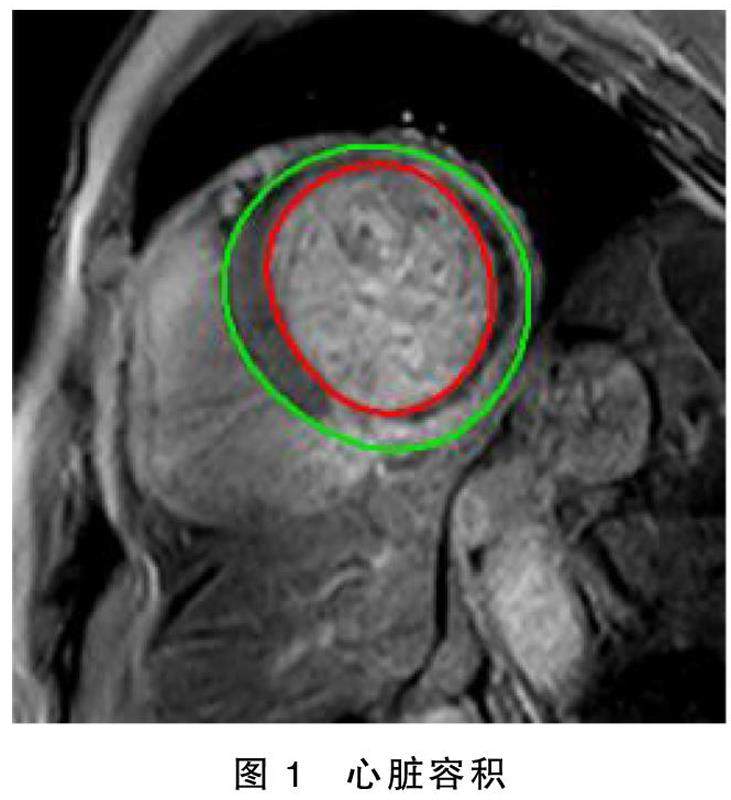

摘要目的:通过心脏磁共振(CMR)定量评估直接冠状动脉介入术(PCI)围术期使用麝香通心滴丸改善ST段抬高型心肌梗死(STEMI)病人冠状动脉微循环及增加存活心肌的效果。方法:本研究为多中心、随机对照、非双盲干预性的临床研究。入选拟进行直接PCI治疗的STEMI病人182例,在进行直接PCI术前随机分为两组:麝香通心滴丸干预组(90例)与对照组(92例),其中,麝香通心滴丸干预组在导管室前给予麝香通心滴丸,并在术后3个月长期口服麝香通心滴丸(每次2粒,每日3次)。(剩余8306字)